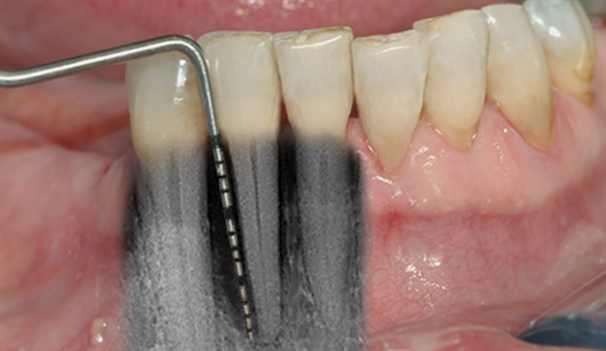

• perio stor 2

perio stor 2

En undersøkelse med lommeregistrering avdekker likevel et omfattende bentap ved den ene tannen.